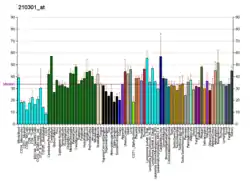

Xanthine dehydrogenase, also known as XDH, is a protein that, in humans, is encoded by the XDH gene.[5][6]

Defects in xanthine dehydrogenase cause xanthinuria, may contribute to adult respiratory stress syndrome, and may potentiate influenza infection through an oxygen metabolite-dependent mechanism.[5] It has been shown that patients with lung adenocarcinoma tumors which have high levels of XDH gene expression have lower survivals.[7][8] Addiction to XDH protein has been used to target NSCLC tumors and cell lines in a precision oncology manner.[8]